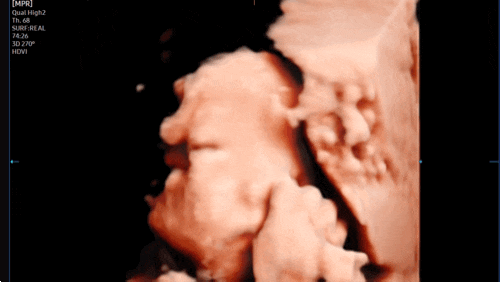

[임신 27주차] 증상, 입체초음파 성공! 극심한 관절통.. 황금기 끝난건가요?

?27주차 증상❤️ 1) 일이 많아 좀 돌아다니면 여지없이 허리랑 생리통배가 끊아지듯 아파서 식겁함ㅠㅠ...